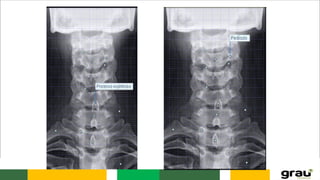

Coluna Vertebral (cervical)

COLUNA VERTEBRAL CURVATURAS: Primáriase secundarias IMPORTÂNCIA CLINICA: hipercifose, hiperlordose escoliose Caracteristicas das vértebras permitem identificar a que região pertencem.